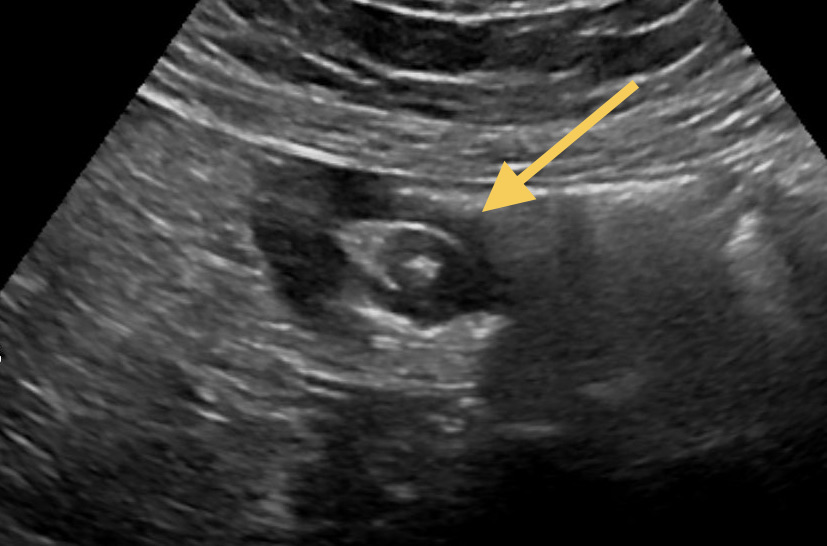

Intussusception of the small intestine occurs when one part of the intestine telescopes into another, causing ischemia and obstruction. This condition is rare in adults, with the most common cause being a benign tumor in the intestinal wall. This paper presents a case of ileal intussusception caused by a submucosal lipoma in the form of a polyp. The intussusception resulted in mild discomfort, and the diagnosis was established through ultrasound and computed tomography scans. Surgical treatment was performed, involving laparoscopic reduction of the intussusception, segmental resection of the intestine, and end-to-end anastomosis. The postoperative course was uneventful.